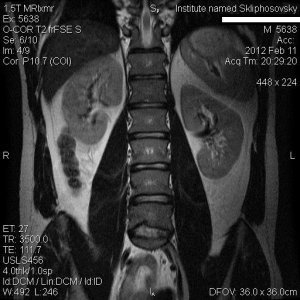

Добрый день, меня зовут Павел, мне 24 года, живу в Москве, военнослужащий. В октябре 2011 год начали беспокоить тянущие боли в пояснице, невролог прописал диклофенак, проколол курс, ситуация не улучшилась. Со временем боль перешла в менее острую, есть напряжение при наклонах вперед, начинает болеть спина в области поясницы при продолжительном сидении без опоры, иногда отдает в заднюю мышцу бедра правой ноги и в верхнюю часть ягодичных мышц обеих ног. В лежачем положении никаких болей и дискомфорта не испытываю. Занимаюсь физкультурой (турник, отжимания, пресс), периодически футбол, волейбол, из-за проблем со спиной стал менее подвижен. Позвоночник никогда тяжестями не нагружал, резко ничего не подымал. Очень прошу врачей этого форума посмотреть мои снимки и высказать свое мнение насчет метода лечения. Заранее спасибо!